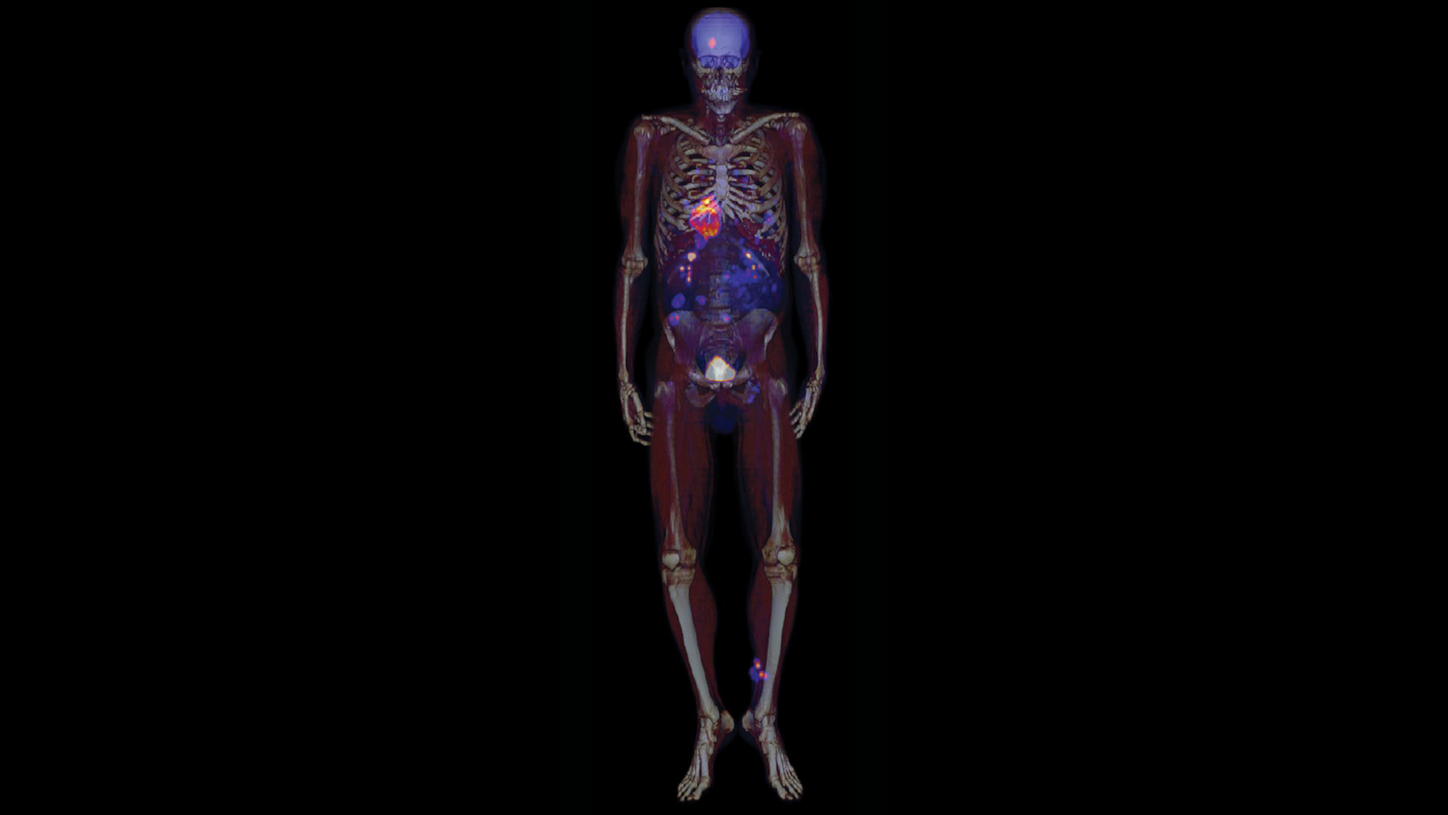

Reflecting on the progress over

the past 25 years, Townsend says

“Nowadays, you have very powerful

instruments compared to what we

had in 2000. And they provide superb,

unbelievable imaging capabilities in

times we didn’t even dream of back in

those days. The development of total body

imaging with large field-of-view

systems is now a reality. We used to

work with 15-cm axial extent, and now

you have a system like Biograph Vision

Quadra, which has 106-cm axial field

of view (aFOV). You can look at

dynamics between different organs,

which we could never do, and that’s

been a tremendous step forward.

Because you know we would image

either the brain or the heart or the liver,

maybe the lungs, lower abdomen—

but the body is a total system.”

2020

Biograph Vision Quadra takes its place as the first 106-cm aFOV whole-body scanner with ultra-high sensitivity, for advanced research, clinical flexibility, and improved patient outcomes. The scanner fits traditional PET/CT spaces while enabling dynamic, multi-organ, and low-dose imaging.